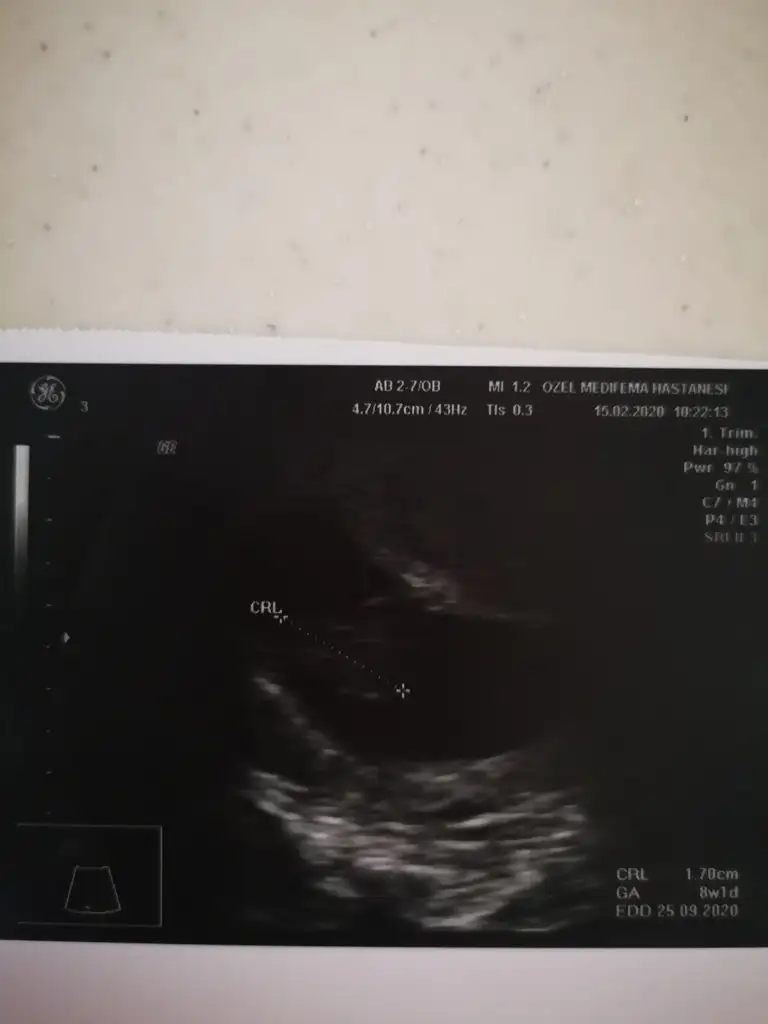

Resim çok net değil ama 8+1 günlük. Cinsiyet tahmini yapabilen varmı bebeğin kesedeki konumuna göre.

Eklentiler

• IMG_20200215_182559.webp

IMG_20200215_182559.webp

10,5 KB · Görüntüleme: 82